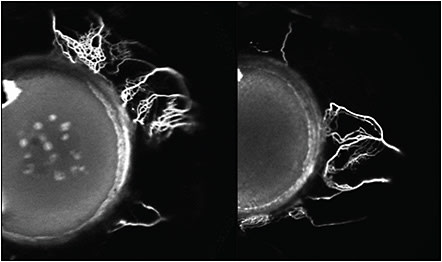

In recent work by Huang et al, details of the structural and functional aspects of the aqueous outflow tract from the anterior chamber to the peri-limbal vessels have been described. By placing a tracer in the anterior chamber during cataract surgery they showed the flow of aqueous humor out of the collector channels and into the perilimbal vessels (Figure 1).6 Huang’s work not only shows the outflow of aqueous humor but also delineates the potential differences in the small vessels within people, which can explain how different anatomic factors can influence the outflow of aqueous humor. It can also show how bypass devices aimed for this region can potentially access collector channels that otherwise may be blocked from a compressed trabecular meshwork.